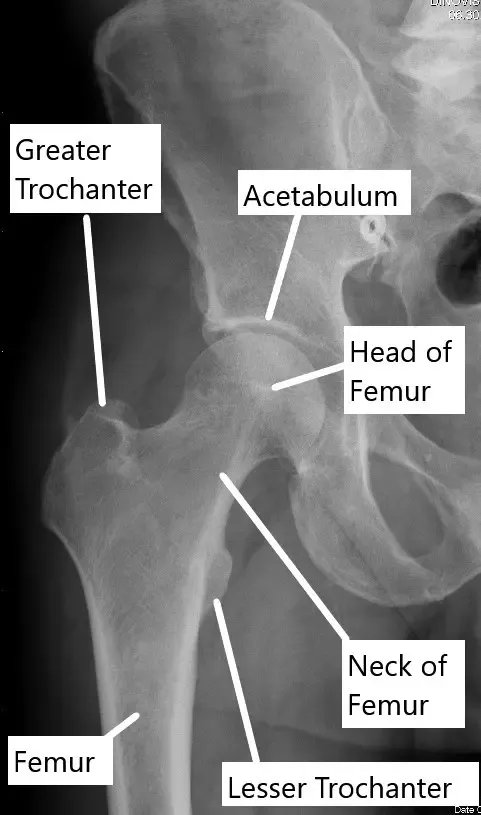

Radiografía que muestra la anatomía normal de la articulación de la cadera.

¿Cómo funciona normalmente una parte del cuerpo? (Anatomía relevante)

La articulación de la cadera es una articulación esférica en la que la cabeza femoral (bola) encaja en el acetábulo (cavidad) de la pelvis. La articulación está estabilizada por una cápsula de ligamentos y músculos, y las superficies están recubiertas de cartílago que permite un movimiento suave. En la osteoporosis transitoria, la cabeza femoral pierde densidad y se vuelve más propensa al dolor y a las lesiones, sobre todo durante las actividades en las que se soporta peso.